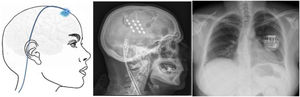

▪Motor cortex stimulation. After localisation of the painful area using MRI, neuronavigation-guided craniotomy is performed with the patient under anaesthesia, and the hand area is located with intraoperative somatosensory evoked potentials. Electrodes (generally a plate with 4 electrodes) may be placed epidurally or subdurally, and are connected to a subclavicular generator with a lead placed via subcutaneous tunnelling (Fig. 8). Efficacy data are based on small series. Of a total of 50 patients, with follow-up times shorter than 40 months, 45%–75% achieved a 50% reduction in pain. Reported complications include infection, epidural haematoma, seizures, and cognitive adverse effects.79

Figure 8.Diagram and radiography images of the skull (sagittal plane) showing the location of the motor cortex stimulation electrode plate and the subclavicular generator in a patient with trigeminal neuralgia refractory to pharmacological treatment, thermocoagulation of the Gasserian ganglion, percutaneous balloon compression, and microvascular decompression (Hospital de la Santa Creu i Sant Pau).